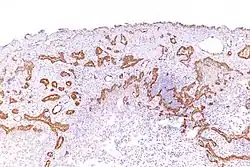

Using immunohistochemistry, calretinin can be demonstrated in both benign mesothelium and in malignant mesothelioma[12][13] and can be used to help differentiate different lung tumours.[14] Antibodies to calretinin can also be used to distinguish between different types of brain tumour, demonstrating only those with neuronal rather than glial, differentiation.[15] Furthermore, the essential function of calretinin in mesothelioma cell lines has been demonstrated in vitro and may be an interesting target for therapeutical approaches.[16]

In Hirschsprung disease, calretinin immunohistochemistry offers additional diagnostic value in specimens with inadequate amount of submucosa and rarely seen ganglion cells. The presence of ganglion cells consistently correlated with calretinin-positive thin nerve fibrils in the lamina propria, muscularis mucosae and superficial submucosa. These calretinin-positive thin neurofibrils are absent in the aganglionic segments of bowel and in the areas without ganglion cells from the junction of normal with diseased rectum. Calretinin is strongly expressed in the submucosal and subserosal nerve trunks in the ganglionic segment. No calretinin expression is seen in the nerve trunks in the rest of the aganglionic segment. It has faint expression in the thick nerve trunks from the areas without ganglion cells. Faint positivity of the thick submucosal and subserosal nerves in the absence of ganglion cells and calretinin positive nerve fibrils, is characteristic of the junction of the aganglionic-to-normal rectum.[17]